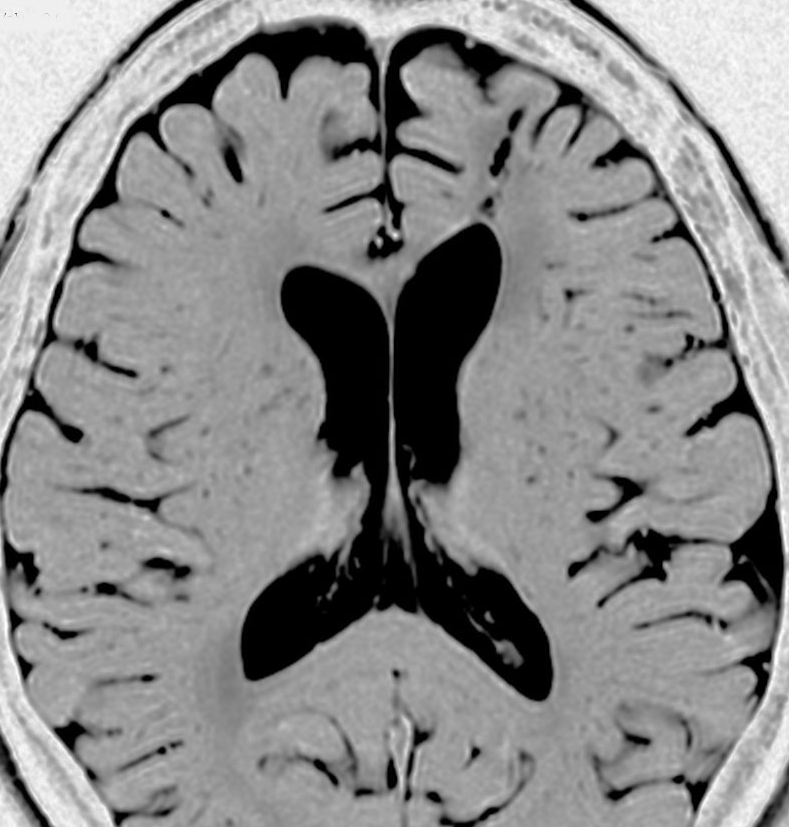

よくみつかる典型的な例です

中年男性に偶然発見された15mmくらいの上衣下腫です。側脳室前角の壁にピッタリくっつくようにキノコのように生えています。下の2枚はガドリニウム造影ですが増強されないのが特徴です。この点で中枢性神経細胞腫 central neurocytomaと区別できます。中枢性神経細胞腫はゆっくりですが大きくなる腫瘍です。でもこのような上衣下腫は大きくなるのはとてもまれです。小さいし水頭症にもならないので,なにも治療しないでほっておきます。間違っても開頭手術などしません。

無症候で偶然発見された左側脳室前角尾状核頭に接したsubependymoma。定位脳生検で病理診断を得たましたが,3年間の観察で徐々に増大しました。左上が発見時,1年後(右上),2年後(左下),3年後(右下)

CTではやや低吸収,T1ガドリニウムでは低信号となりガドリニウム増強されません。小さな上衣下腫の場合は等吸収あるいは等信号のものも多いです。小さく点状に造影されている部分があるがこれは定位脳手術痕(track)です。